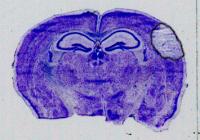

Treatment with Gap 19

image: The researchers used a molecule called Gap19 to block the hemichannels, in the same stroke model, which resulted in smaller stroke damage. view more

Credit: University of British Columbia

For the study, the researchers used a genetic approach that mutated the channel proteins, called connexins, in such a way that blocks the formation of hemichannels. This allows the astrocytes to protect the neurons, significantly reducing the size of the stroke injury in the brain. The researchers also used a molecule called Gap19 to block the hemichannels, in the same stroke model, which also resulted in smaller stroke damage. Together, the two approaches demonstrate that connexin hemichannel blockers could be used as a neuroprotective agent in stroke.